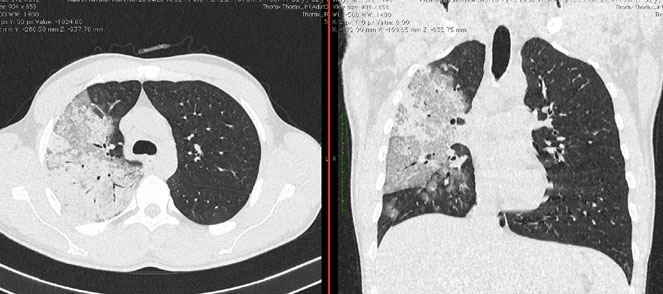

Методы лучевой диагностики применяют для выявления COVID-19 пневмоний, их осложнений, дифференциальной диагностики с другими заболеваниями легких, а также для определения степени выраженности и динамики изменений, оценки эффективности проводимой терапии.

КТ имеет высокую чувствительность в выявлении изменений в легких, характерных для COVID-19. Применение КТ целесообразно для первичной оценки состояния ОГК у пациентов с тяжелыми прогрессирующими формами заболевания, а также для дифференциальной диагностики выявленных изменений и оценки динамики процесса. КТ позволяет выявить характерные изменения в легких у пациентов с COVID-19 еще до появления положительных лабораторных тестов на инфекцию с помощью МАНК. В то же время, КТ выявляет изменения легких у значительного числа пациентов с бессимптомной и легкой формами заболевания, которым не требуется госпитализация. Результаты КТ в этих случаях не влияют на тактику лечения и прогноз заболевания при наличии лабораторного подтверждения COVID-19. Поэтому массовое применение КТ для скрининга асимптомных и легких форм болезни не рекомендуется.

Вместе с тем, комплексная оценка анамнестических, клинических и рентгенологических данных позволяет определить клинически подтвержденный случай COVID-19, маршрутизировать пациента и начать противовирусную терапию.

3. Применение лучевых методов у пациентов с симптомами ОРВИ легкой степени тяжести и стабильном состоянии пациента, возможно только по конкретным клиническим показаниям, в том числе при наличии факторов риска, при условии достаточных технических и организационных возможностей. Методом выбора в этом случае является КТ легких по стандартному протоколу без внутривенного контрастирования или РГ при ограниченной доступности КТ. Использование УЗИ в этих случаях нецелесообразно. Применение КТ исследования в сроки ранее 3 - 5 дней с момента появления симптомов заболевания является нецелесообразным.

4. Все выявляемые при лучевых исследованиях признаки, включая КТ-симптомы, не являются специфичными для какого-либо вида инфекции и не позволяют установить этиологический диагноз. Вне клинической (эпидемической) ситуации они не позволяют отнести выявленные изменения к пневмонии COVID-19 и дифференцировать их с другими пневмониями и невоспалительными заболеваниями. Данные лучевого исследования не заменяют результаты обследования на РНК SARS-CoV-2. Отсутствие изменений при КТ не исключают наличие COVID-19 и возможность развития пневмонии после проведения исследования.

15. Рекомендации по формированию описаний и оценке изменений в легких и ОГК при имеющейся/подозреваемой пневмонии COVID-19 представлены в Приложении 1.